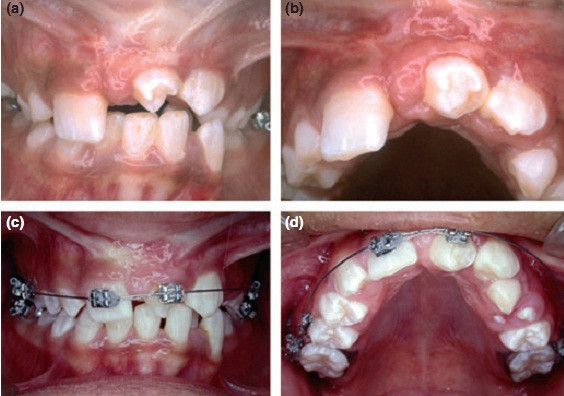

女,十岁,单侧唇腭裂致21牙、22、12牙畸形,且21牙、22牙间牙槽骨发育不全。经自体髂嵴骨移植后,拔除21牙、22牙行正畸治疗以将23牙移动至22牙位置。同时将正畸需拔除的下颌第一前磨牙移植到21牙的牙槽窝内。并在正畸治疗结束后树脂恢复21牙、22牙形态。患者18岁时拔除左上颌乳尖牙行种植义齿修复。